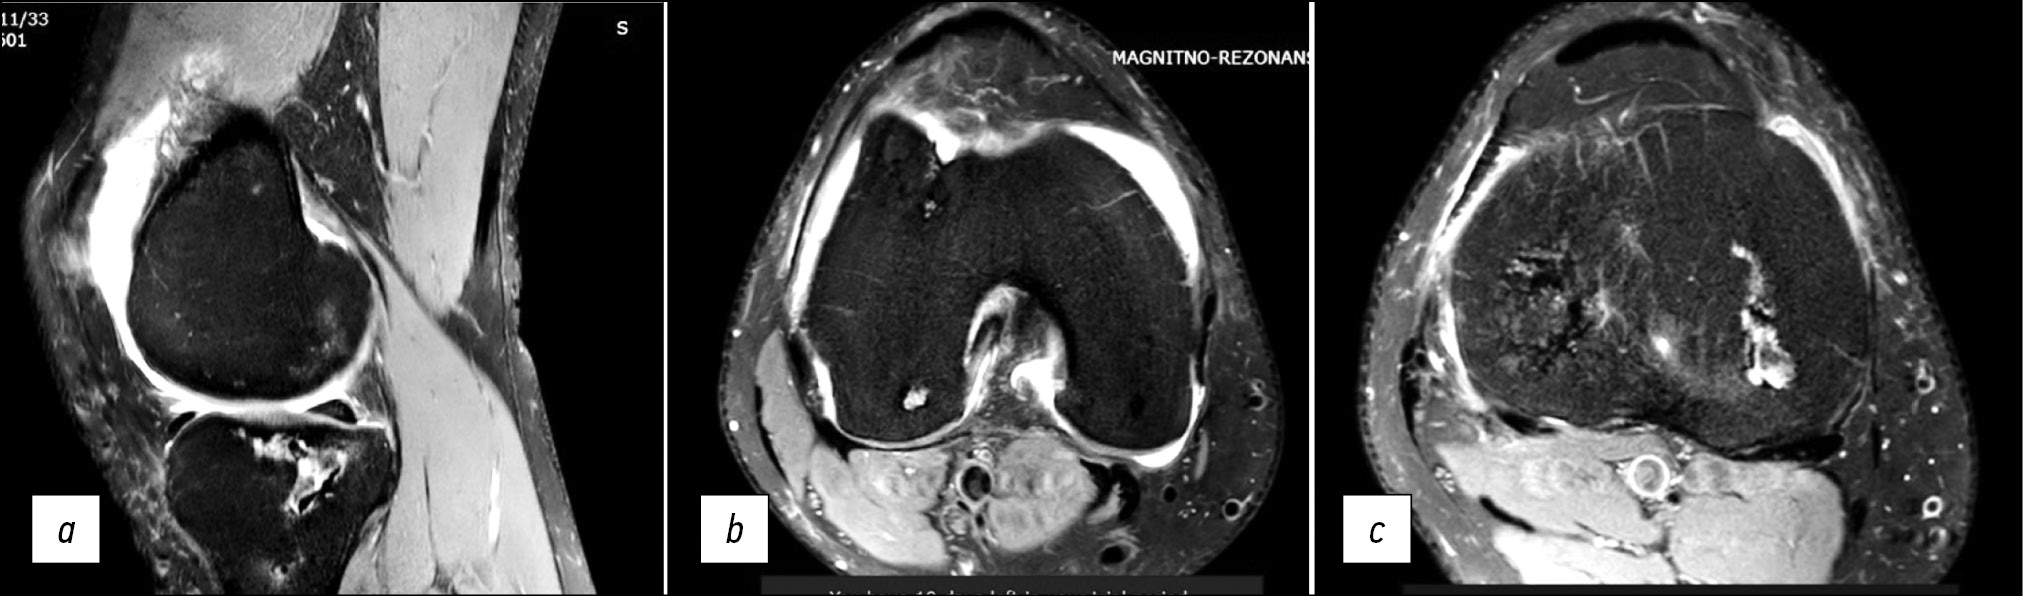

Aseptic necrosis is more common in patients with severe disease, with an incidence of 5% to 58%. Avascular bone necrosis is one of the adverse symptoms of SARS-CoV-2. Avascular necrosis can be detected from 7 days to 2 months from the onset of coronavirus. There was no relationship between the severity of SARS-CoV-2 and the onset of avascular necrosis. The lesion affects all major joints (hip, knee, shoulder, spinal joint, and sacrum), and can be diagnosed by MRI (Fig. 6, 7). Patients treated with corticosteroids for a long time or with higher doses had an increased risk of osteonecrosis [31, 32].

Fig. 7. Aseptic necrosis of the tibial and femoral condyles in a 22-year-old patient infected with coronavirus. Sagittal (a) and axial (b, c) magnetic resonance imaging slices.